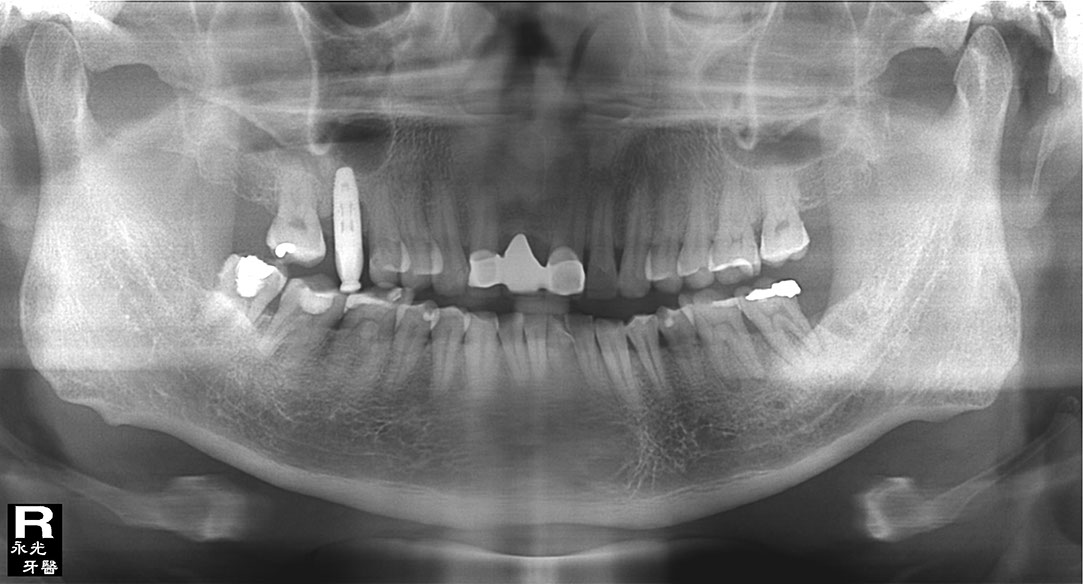

Implant 48i3.jpg

光牙醫